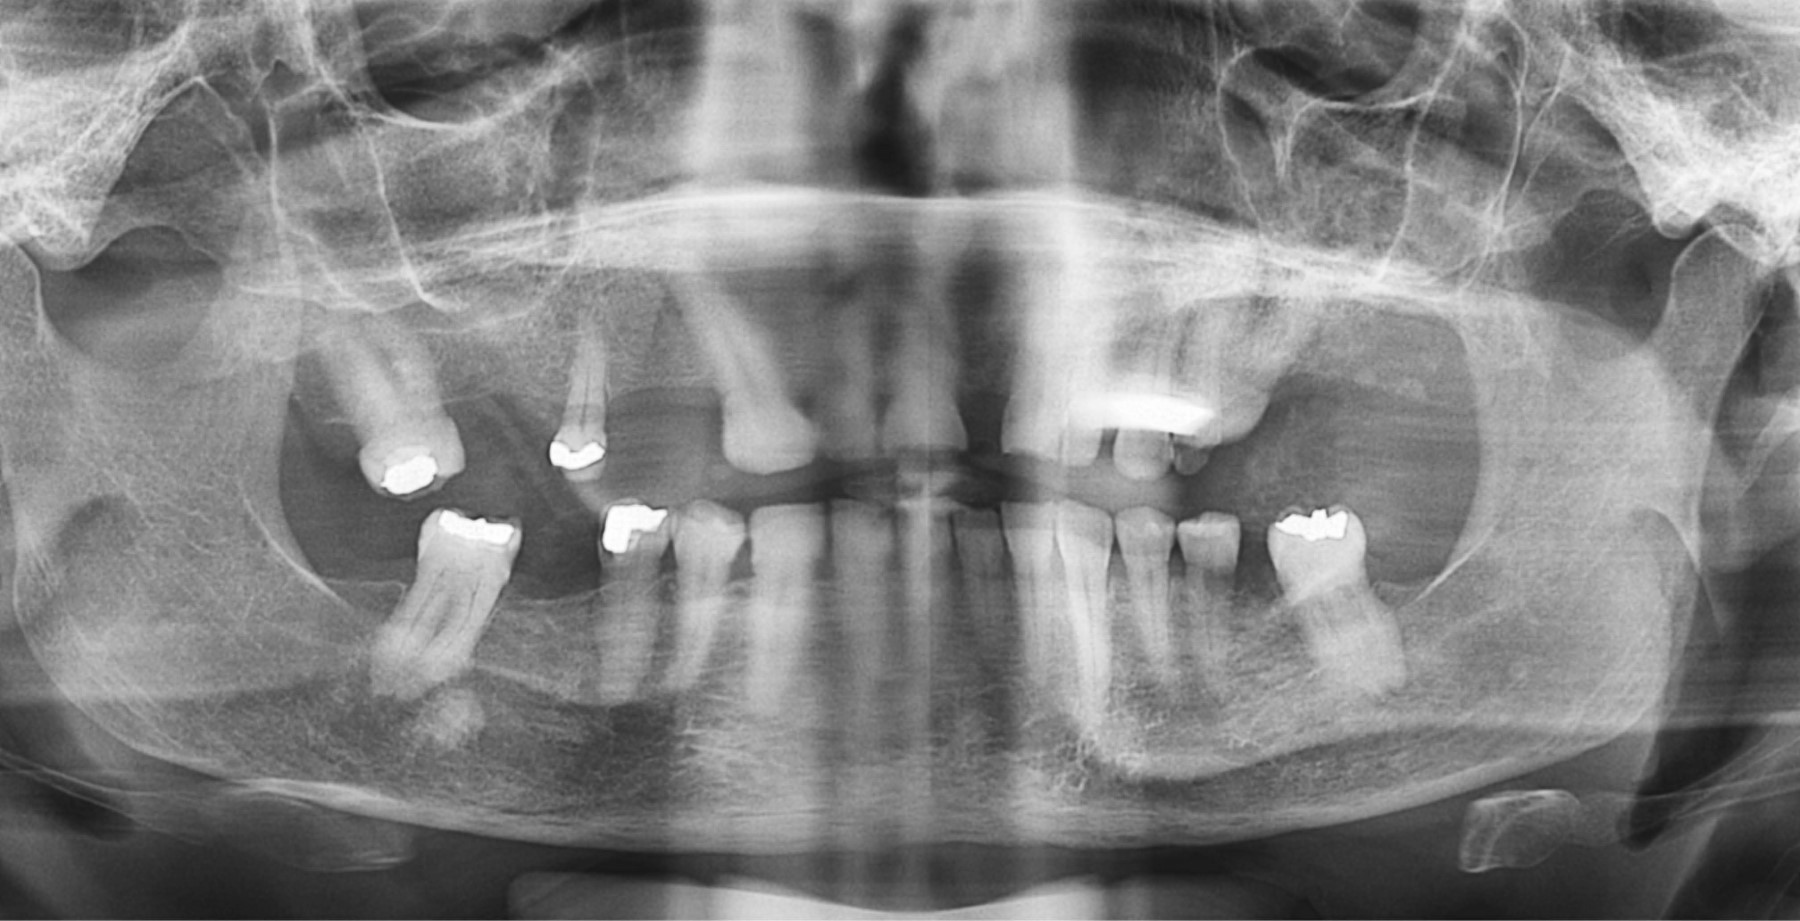

Una vez analizados los errores, se pudo clasificar a las radiografías por su calidad, en ese sentido 69% fueron catalogadas como inaceptables, 31% como aceptables y ninguna pudo ser clasificada como excelente.

Por otra parte, al correlacionar las variables se encontró que hay variables que contribuyen en mayor proporción a la clasificación de una radiografía como deficiente, tales como: mentón hacia arriba, paciente demasiado hacia atrás e imágenes fantasmas, como se aprecia en el Figura 1.

Se debe destacar que los diferentes tipos de errores no contribuyen de manera uniforme en la clasificación de una radiografía como aceptable o inaceptable para diagnóstico. Las variables que contribuyen principalmente a la clasificación de una radiografía como inaceptable son: mentón hacia arriba, imagen fantasma, mentón hacia abajo, paciente hacia atrás y hacia adelante, como se puede constatar en la Figura 3.

Cuando comparamos la cantidad de errores y porcentaje de radiografías aceptables y deficientes, observamos que a medida que se suman errores a la radiografía éstas son más deficientes (Tabla 5). Sin embargo, existen radiografías aceptables incluso con cuatro y cinco errores (Figura 4), por lo que no se puede establecer una relación directa entre el número de errores y la calidad de las radiografías, a pesar de que al aumentar la cantidad de errores la radiografía tiende a tener mayor probabilidad de ser inaceptable, todos éstos podrían ser errores leves que no le resten valor diagnóstico al examen, por el contrario, se puede tener un único error muy marcado o de gran magnitud en una radiografía que la haga inaceptable al imposibilitar un correcto diagnóstico.

Adicionalmente clasificó 69% de las panorámicas como inaceptables, lo que representa un valor muy por arriba del promedio descrito en una revisión sobre la tasa de rechazo de imágenes radiográficas en radiología dentomaxilofacial, en la cual las panorámicas rechazadas representaron 4.10% con un rango que osciló entre 2.89 y 11.65% en esta revisión sistemática.8 Otros estudios similares al presente mostraron un mayor porcentaje de radiografías clasificadas como inaceptables, con 36.7,9 24.96 y 15.08%.7

Los errores que contribuyen principalmente a la clasificación de una radiografía como inaceptable son: mentón hacia arriba, imagen fantasma, mentón hacia abajo, paciente hacia atrás y hacia adelante.